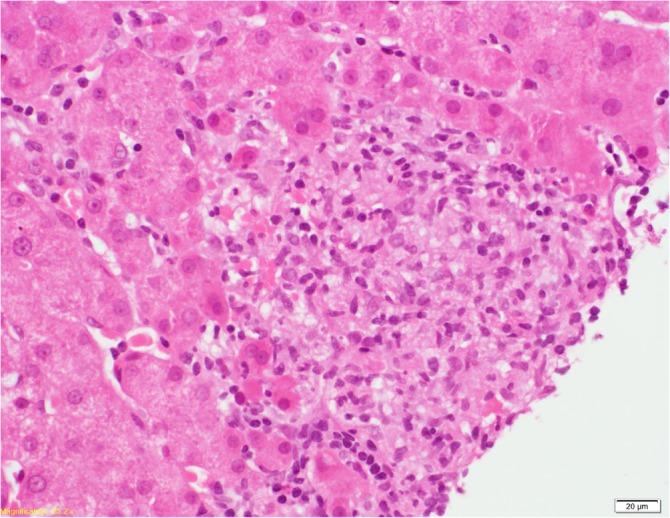

A 68-year-old gentleman presented to hepatology department with asymptomatic year-long history of stably deranged liver function tests. His peak alkaline phosphatase (ALP), was 828 with alanine transaminase (ALT) of 141. Full liver workup was negative; hence, a liver biopsy was organised, which confirmed giant cell hepatitis (GCH). A computed tomography (CT) scan revealed non-specific interstitial pneumonitis (NSIP) pattern interstitial lung disease supported by lung function tests. Antibody testing showed strongly positive antinuclear antibody (ANA) with anti-polymyositis/scleroderma (anti-PM-SCL) antibody. Clinical picture was in keeping with likely undifferentiated connective tissue disease (UCTD) with polyarthralgia, early morning stiffness, Raynaud's and nailfold infarcts with capillaritis on nail bed examination. Further testing confirmed triple-positive antiphospholipid antibodies twice 12 weeks apart (immunoglobulin M [IgM] anti beta-2 glycoprotein antibodies, lupus anticoagulant and IgM anticardiolipin antibody). He was treated with mycophenolate and hydroxychloroquine with resolution of symptoms. Giant cell hepatitis is uncommon, with only 100 cases reported worldwide. To our knowledge, this is the only report of GCH in the context of UCTD, highlighting the significance of careful evaluation of liver disease overlap and the successful role of mycophenolate mofetil (MMF) in this setting.

https://cdn.ncbi.nlm.nih.gov/pmc/blobs/776d/7241662/b8fafbb99921/MJR-30-4-224-g001a.jpg